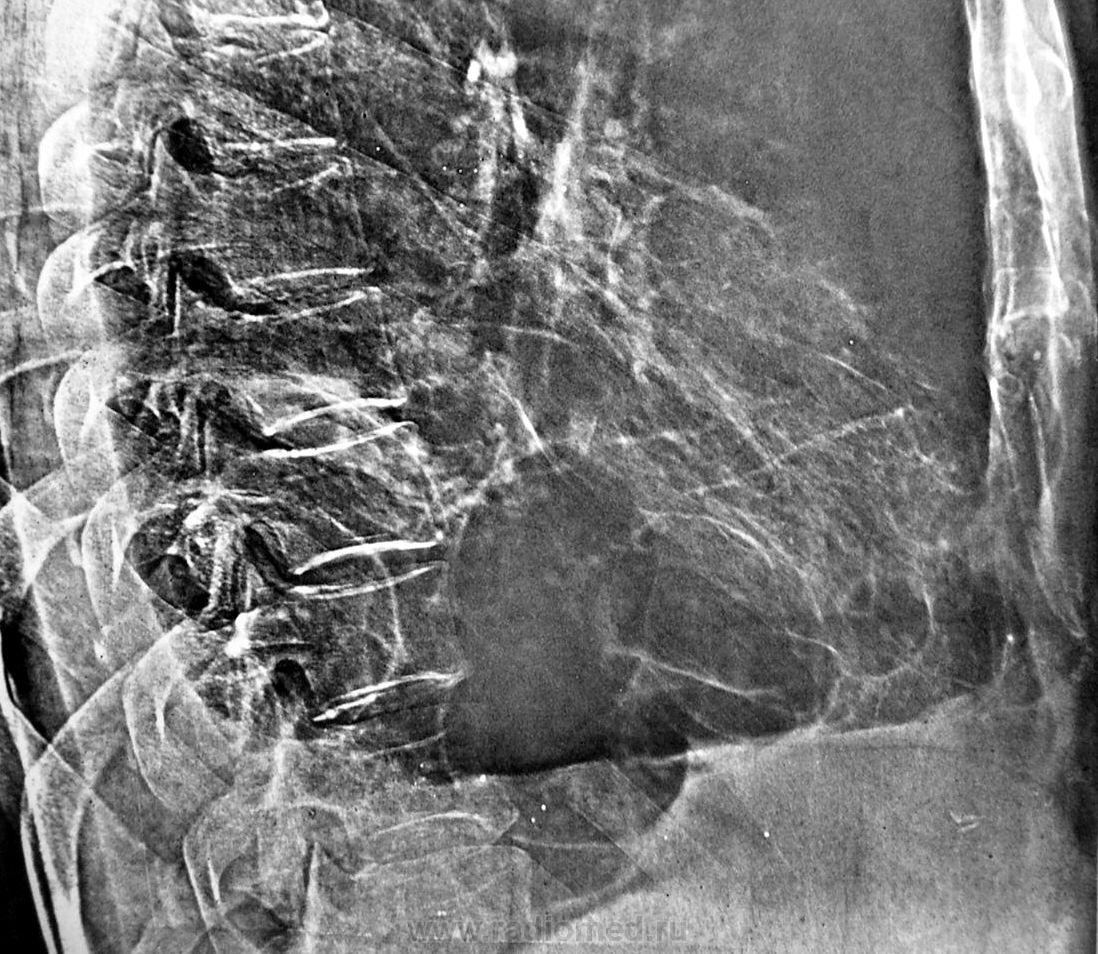

Год назад появились локальные изменени внизу справа.

Поликистоз нижней доли правого лёгкого.

Можно спороть хохму - назвать и "буллёз".

Однако, буллы логичнее.

Частичная облитерация синусов, конечно, несколько смущает.

Хотя, с учетом наличия консолидированных переломов справа, возможна и другая версия.

Но обычно такие буллы развиваются в верхних отделах легких, а в этом случае локально внизу. Возможно правильно подумать и о связи с травмой - но нет архива...

Может, остаточные плевральные полости? Без линейной томографии не определить, в плевральной полости или в субплевральных отделах. Для исключения диафрагмальной грыжи можно было контрастировать ЖКТ. Но раз архив, буду с нетерпением ждать верного ответа

Травма - перелом ребер + ушиб легкого - гемоторакс + пневмония - обратное развитие - пневмосклероз + плевральные наслоения - облитерация мелких бронхов - клапанная обструкция мелких бронхов - псевдокисты (буллы). Таких схем можно придумать множество. Без анамнеза - пустое дело.

Выскажу простую гипотезу, может быть кто-то разовьёт. Поскольку в образовании булл имеет значение клапанный механизм, можно предположить, что год назад он появился. Например эндобронхиальная опухоль в бронхе базальной пирамиды. Боковая проекция вроде бы подтверждает такое предположение.